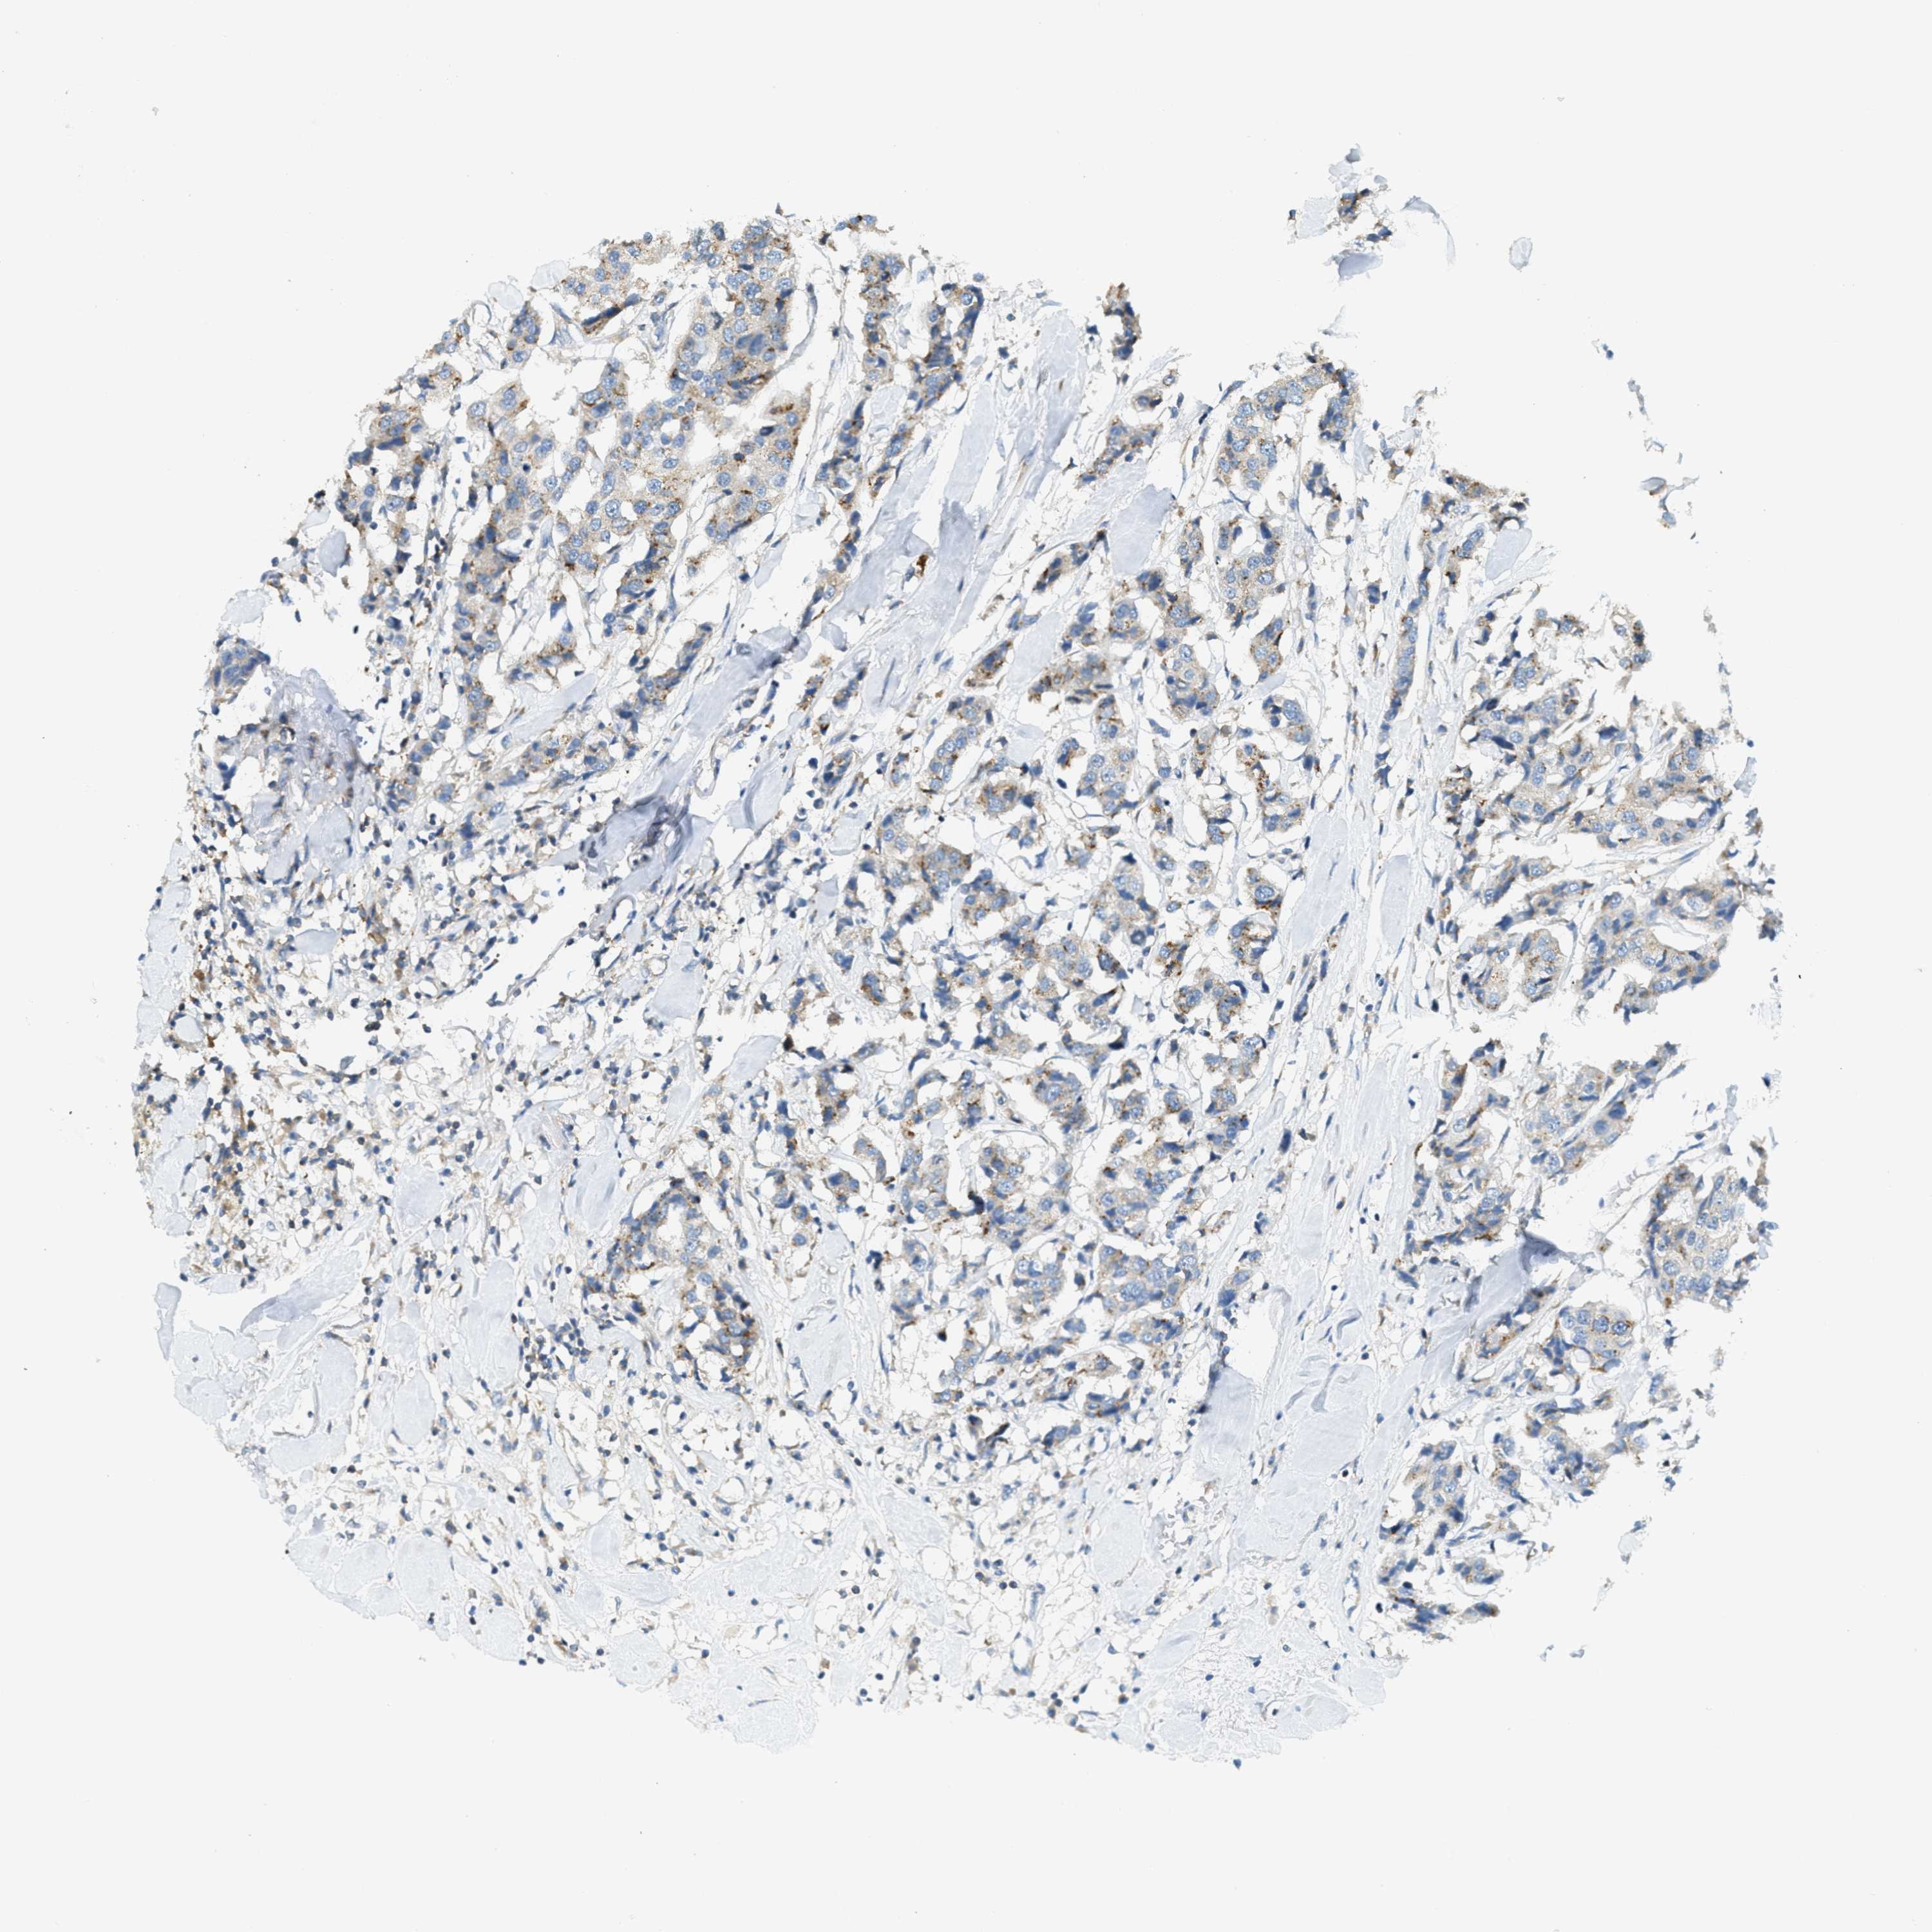

CANCER BREAST CANCER Show tissue menu

BRCA TCGA BRCA VALIDATION PROTEIN EXPRESSION